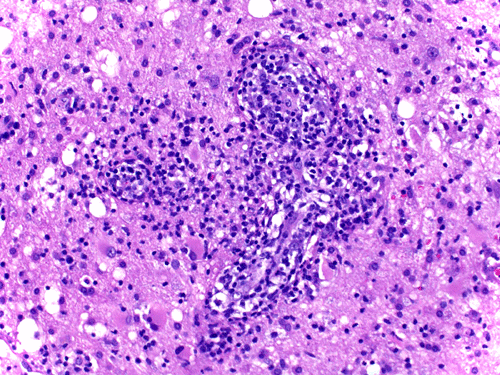

Histopathology: There is a necrotizing process with granulomatous reaction and perivascular lymphocytic infiltration. In some areas, there is concentric, perivascular lymphocytic infiltration surrounded by a granulomatous reaction (Panel A). On higher magnification, the lymphocytic infiltration appears to contain both small lymphocytes and scattered atypical cells with increased mitotic activity (Panel B and C). No definitive viral inclusion bodies are identified.

Special stains and Cultures: GMS stain, AFB stain, and immunohistochemistry for toxoplasma were negative. The large atypical cells were positive for CD20 (Panel D), and to a lesser extent CD30 and Epstein-Barr virus (EBV). Immunohistochemistry for CD68 highlighted numerous histiocytes, including those within vague granulomas. Numerous reactive T-cells were demonstrated by immunohistochemistry for CD45RO, CD2, CD3, CD5, CD7, and CD8, but not CD4.